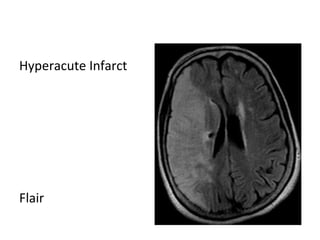

-FLAIR may be normal , subtle hyperintensity may be

seen on FLAIR

Hyperacute Infarct

T1

T2

Flair

DWI

ADC